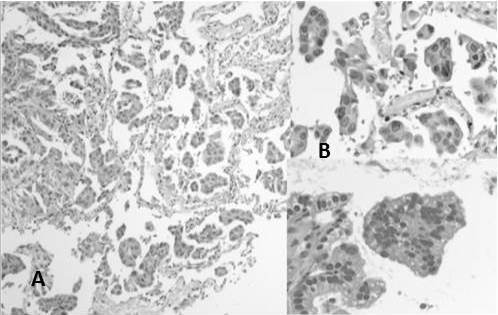

En la reclasificación los casos de ADC estuvieron representados por: ADC patrón predominantemente sólido 57,3 % (Figura 3 y 4), ADC patrón acinar 18,2 % (Figura 5) y en menor frecuencia ADC con patrones mixtos como: patrón predominantemente sólido y acinar 3,6 %, ADC patrón predominante sólido con células en anillo de sello 2,7 %, ADC patrón predominante acinar y micropapilar (Figura 6), patrón predominantemente acinar y sólido, papilar y acinar y patrón predominantemente papilar (Figura 7) cada uno con 1,8 %, asimismo, se encontraron en menor cantidad los siguientes patrones: lepídico no mucinoso (Figura 8) tipo intestinal (Figura 9), mucinoso (Figura 10), y otros patrones mixtos con 0,9 % cada uno (Cuadro 4)

Al reclasificar los casos de ADC de pulmón se encontró el patrón predominantemente sólido 57,3 % como el más común en segundo lugar el ADC patrón acinar 18,2 % y en menor frecuencia: ADC patrón predominantemente sólido y acinar 3,6 %, ADC patrón predominante sólido con células en anillo de sello 2,7 %, ADC patrón predominante papilar, otros patrones mixtos y tipos menos frecuentes. Esto se asemeja a lo encontrado Tsao y col. (10) en el estudio LACE-Bio el cual es el estudio de cohorte multinstitucional más grande hasta el momento en el que se reclasificaron 575 casos de ADC de pulmón para predecir el beneficio de la quimioterapia adyuvante en pacientes sometidos a resección completa obteniendo de igual forma el subtipo predominantemente sólido como el más común con 46 % seguido en secuencia del subtipo predominantemente acinar 26 % siendo este primero equivalente a carcinomas pobremente diferenciados sin ninguna característica de diferenciación reconocible morfológicamente y determinando un peor pronóstico para el subtipo sólido y micropapilar (semejante a lo observado en mama) con una supervivencia más baja y respuesta pobre al tratamiento (10) . De forma similar Warth y col. (19) reclasificaron 100 casos de ADC pulmonares con el fin de determinar la variabilidad inter-observador de la clasificación propuesta por IASLC / ATS / ERS para los ADC pulmonares obteniendo de igual manera el subtipo predominantemente sólido como el más frecuente (37 %), seguido de acinar (35 %), lepídico (20 %), papilar (5 %) y micropapilar (3 %) este resultado de igual forma se asemeja al nuestro con una población similar. Análogo a nuestro resultado también Warth y col. (20) realizan otro trabajo de investigación reclasificando 40 casos de ADC pulmonar con el propósito de determinar la concordancia teniendo en cuenta la nueva clasificación y encontró el subtipo predominantemente sólido, más frecuente con mayor nivel de concordancia.

Entre los otros tipos de ADC encontrados en nuestro estudio es interesante destacar que el patrón micropapilar no se encontró por separado observándose con otros patrones que resultaron tener mayores o iguales porcentajes en la muestra, a pesar de esto como lo establece la OMS del año 2015 es importante documentar el porcentaje de componentes que se encuentran en menor proporción en la muestra porque incluso la presencia en pequeños porcentajes de patrón micropapilar está asociado con mal pronóstico mayor tendencia a metástasis ganglionar, invasión pleural y recidiva (4); en nuestro caso el patrón micropapilar estuvo presente en tres casos con porcentajes variables entre 5 % y 50 % asociado a componentes acinares y sólidos. Kamiya y col. (22) estudiaron 383 casos de ADC de pulmón con porcentajes diversos de patrón micropapilar en la muestra y observaron a partir de las curvas de supervivencia que el pronóstico fue peor con el aumento de la proporción de ADC micropapilar en los tumores en comparación con el grupo sin patrón micropapilar en la muestra, de igual forma Cakir y col.(23)han indicado que la presentación de ADC micropapilar es un predictor de resultados desfavorables no solo en ADC de etapa temprana sino también en ADC de etapa tardía, por el contrario Clay y col. (24) manifiestan que la morfología micropapilar por sí sola no es indicativa de mal pronóstico si no que depende del estadio tumoral siendo peor en estadios III y IV.